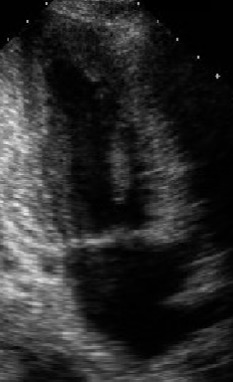

<p>What view is this?</p>

Subcostal 4ch